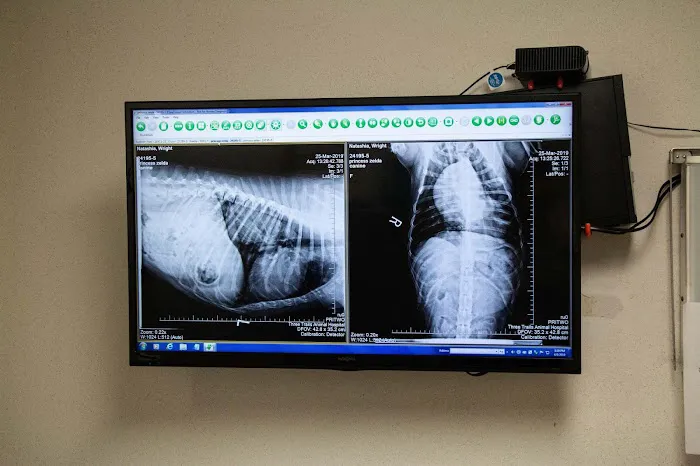

The team at Three Trails Animal Hospital understands that caring for a pet can sometimes be stressful, which is why they have integrated **Low-Stress Handling** techniques into their daily practice. Their goal is to create a calm and supportive environment for both the animals and their owners. As a **Full Service Vet Clinic**, they utilize modern technology, including a fully-equipped surgical suite, **Digital Radiography (X-Ray)**, and an **In-House Diagnostic Laboratory**, allowing their experienced veterinarians and registered veterinary technicians to deliver timely and accurate care. One client’s heartfelt apology for pushing to have their frantic puppy seen, along with their gratitude to the staff for assurance that their pet would survive a serious, disorienting incident, highlights the hospital’s ability to handle high-stress situations with professionalism and effective medical intervention.

- **Advanced Diagnostics & Imaging:** Digital Radiography (X-Ray), Ultrasound, In-House Diagnostic Laboratory, Blood Pressure Monitoring, Capnography, Pulse Oximetry, Allergies and Dermatology Testing, and Malignancy Detection.

- **In-House Technological Capabilities:** The presence of an **In-House Diagnostic Laboratory**, **Digital Radiography**, and **Ultrasound** allows for rapid, thorough diagnostics, accelerating the treatment process, especially crucial during sick visits and emergency evaluations.

- X-Ray

- Digital Radiography